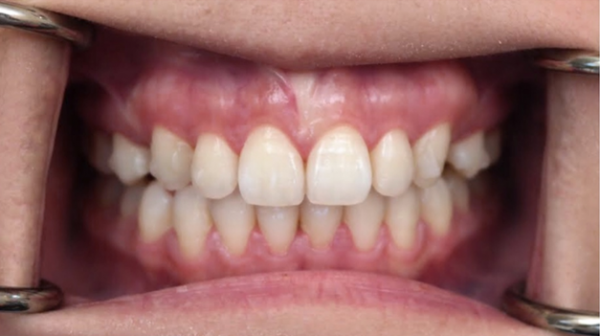

下图是我带上牙套后的样子,基本上是看不出来的,可以说是非常隐形了!

有图有真相

3.15是我安装牙套的第一天,到10.16号已经整整七个月了,不管是牙齿上的改变,和脸部的改变都还蛮大的,许久不见我的朋友都会觉得我变了个人,也很多人说我脸瘦了,其实人家不是胖啦,只是肉很多!不多说,上图

2017.03.15

2017.08.02

2017.10.17

其实还有20个牙套,但是我的凸牙已经基本上都回去了,改变巨大。下面放羞羞的真人图。

比较明显的是我的人中明显变长,嘴突有了很大改善,下巴也因此显得更长,我发现最惊喜的改变是,我的肉肉脸!!!没有了!!!

有人说我瘦了,其实我3月份的时候97斤,现在105斤,所以并不是我的体重,而是我整个脸的变化,我也是有下巴的人了!

矫正牙齿到现在,真的是所见即所得,和付出的相比,得到的实在是太惊喜了。还有很长的路要走,还有20个牙套要戴,但是我觉得忍不住想把这种喜悦分享给大家,相信高科技!相信黄医生!